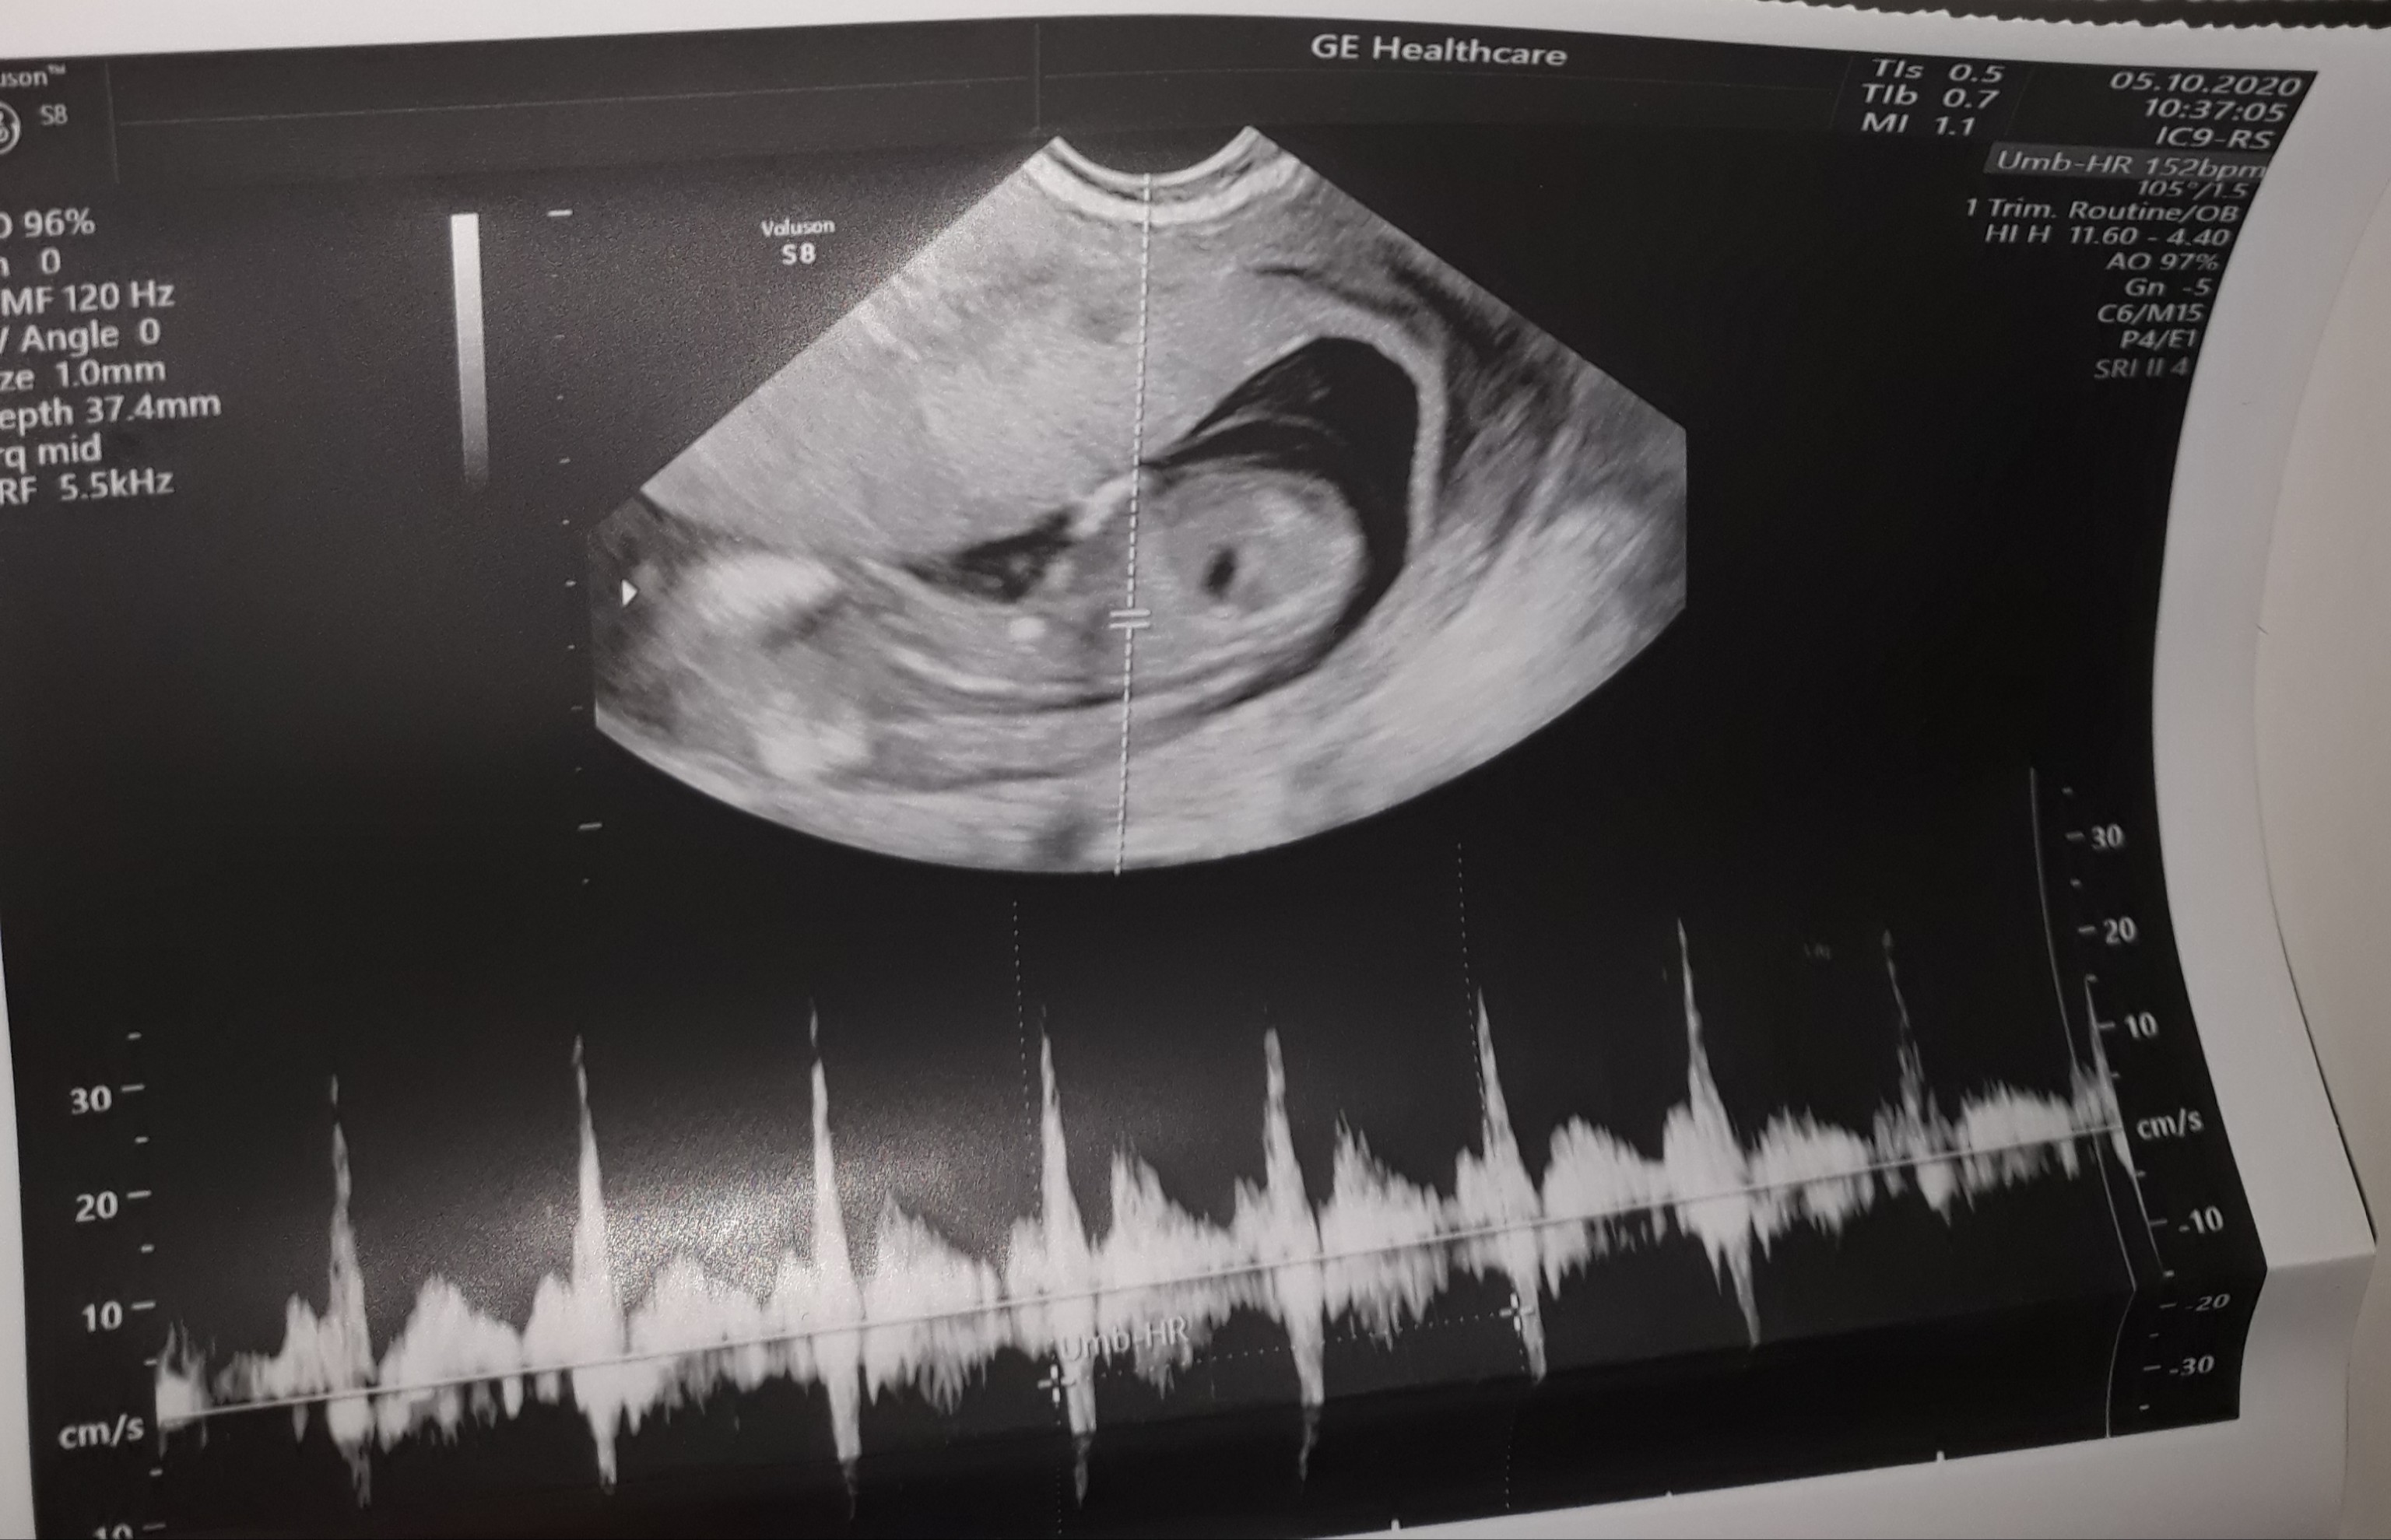

Tylko takie zdjęcie masz ? Wygląda trochę jakby była próba łapania przezierności, ale dziwnie nie bokiem tylko tyłem, to drugie chyba jest z pomiarem crl i wygląda na pierwszy rzut oka lepiej, ale też bez szału. Dzidzuś się mocno ruszał? Słabe to zdjęcie, a to ważne usg, masz opis taki porządny ze wszystkimi pomiarami itd.? Jak nie to może powtórz u kogoś z lepszym sprzętem...

To jest kolejne zdjecie z serduszkiem albo jakimiś przepływami, nie masz żadnego papierowego opisu do zdjęć? To było u Twojego prowadzącego czy gdzieś zewnetrznie robiłaś samo usg? Robiłaś test pappa? Czasem jest tak że opis dają dopiero po wynikach skorygowanych z pappa, ale to byś chyba wiedziala?

Przemyśl w takim razie czy nie zrobić gdzieś jeszcze prenatalnego u specjalisty z certyfikatem... Może to tylko kwestia zdjęć/sprzętu czy coś ale to zdjęcie nie wydaje się być dobre na oko laika- np. moje dziecko na obydwu usg wykonywanych w podobnym czasie wyglądało inaczej. Nie zrozum mnie źle - nie chce straszyć ani żebyś się bez sensu martwiła, ale nie masz żadnej informacji ani opisu, a tak też nie powinno być.